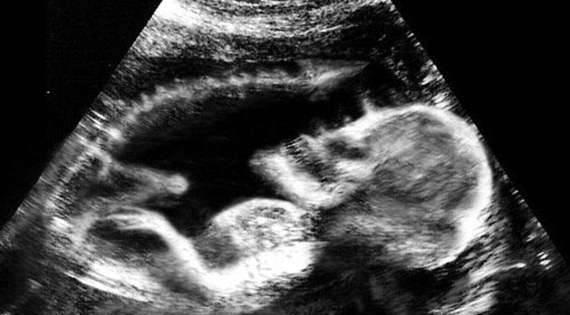

▼一副弱小的骨架配上巨大的不协调的头部,和身体的大小不成比例,这看上去有点像外星人的造型。